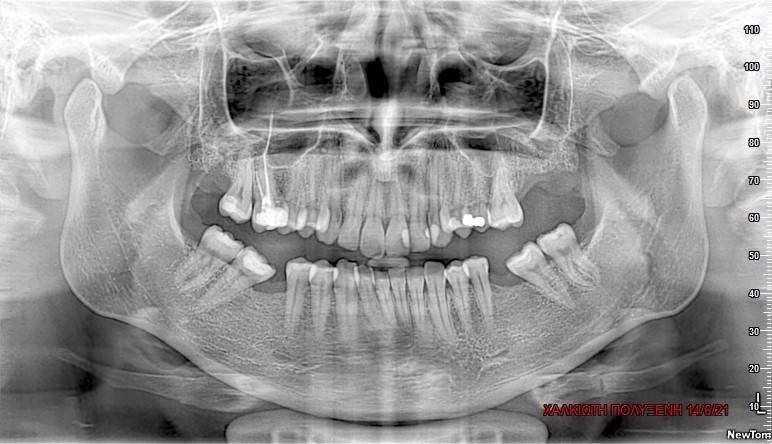

Προκύπτει όταν κάποια δόντια λόγω έλλειψης χώρου ή λάθος θέσης στο οστό δεν μπορούν να ανατείλουν.